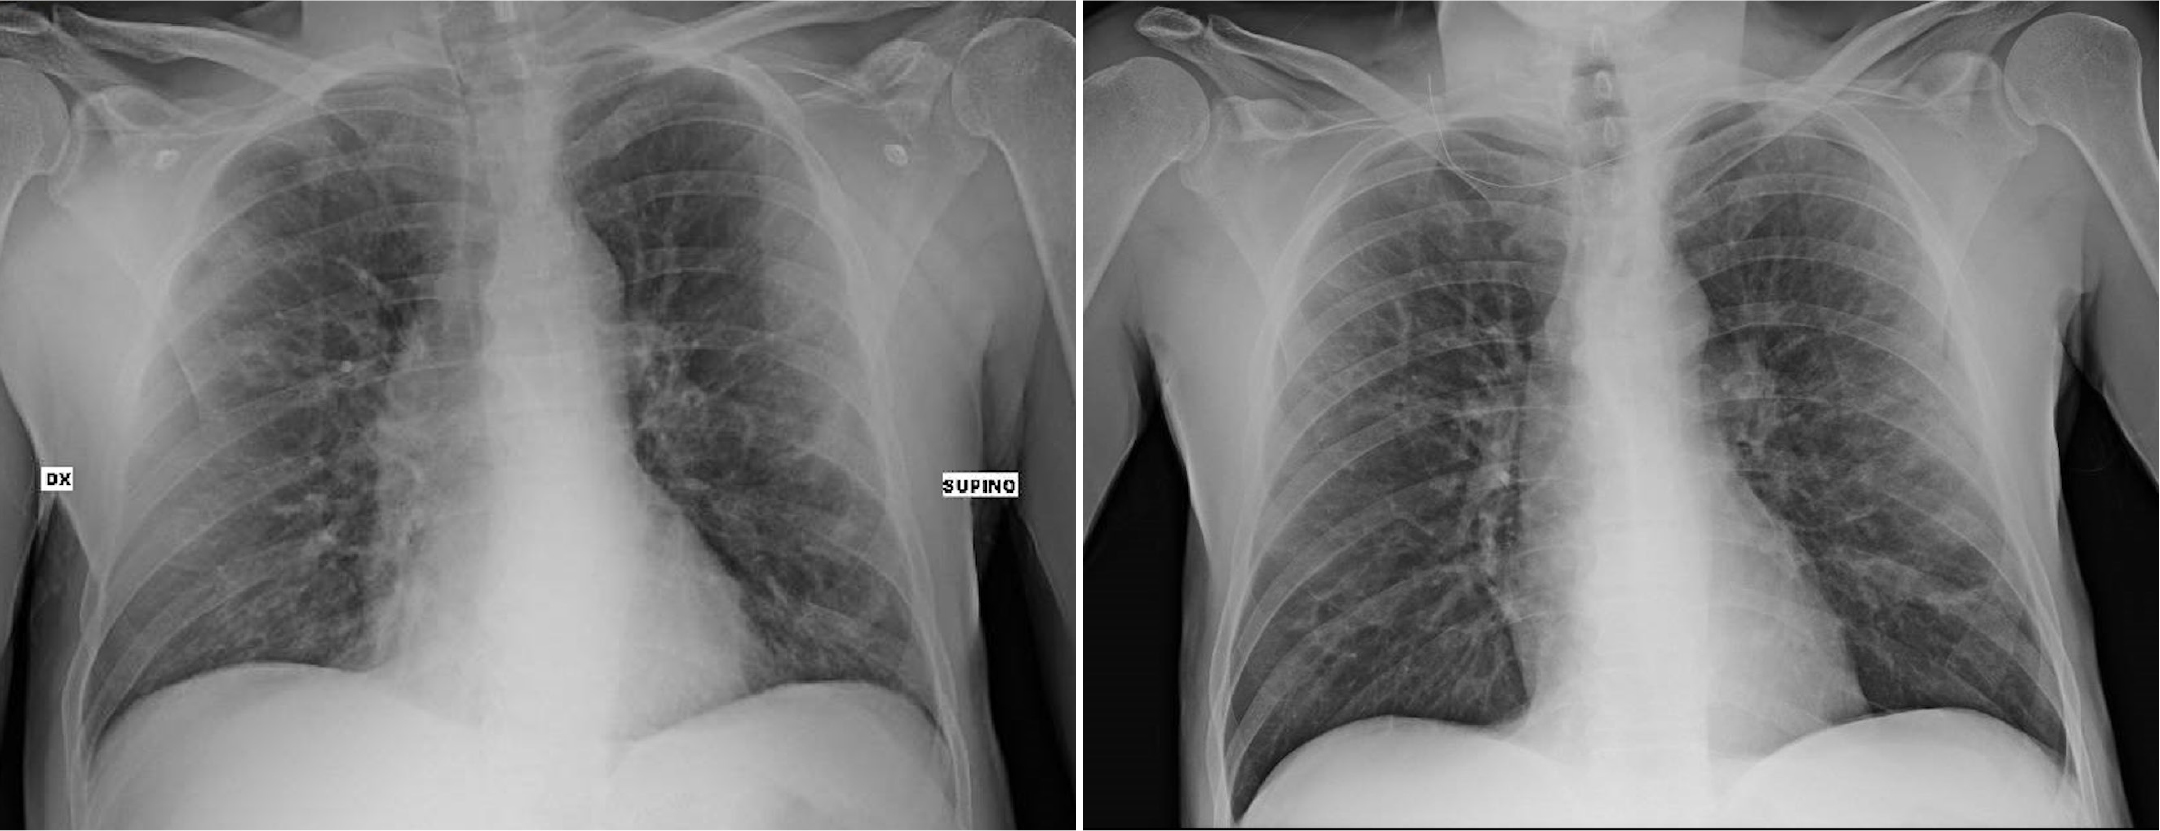

Lung ultrasound showed a suggestive pattern of interstitial lung disease associated with bilateral subpleural consolidations in the postero-inferior scans (Figure 1, 2). The total Lung Ultrasound Score (LUS) was 10. Chest x-ray, performed at the admission, showed a mild thickening of the peribronchovascular interstitium with focal areas of consolidation in the right medio-superior and left medio-inferior regions, compatible with a viral interstitial pneumonia (Figure 3).

Figure 3: Chest x-ray at the admission (left) compared to that at the hospital discharge day (right).

On April 7 a second chest x-ray was performed, showing a mild thickening of the peribronchovascular interstitium in the left middle-inferior field. (Fig 3). He was dismissed on April 8 in good clinical conditions, with an indication of a follow-up visit for HIV control.

As detailed above, our patient developed a COVID-19 dependent interstitial lung syndrome, documented by lung ultrasound and chest x-ray upon arrival in the Emergency Department. As expected, blood test pattern was typical for COVID-19, such as lymphocytopenia (<1.5 x103/µl), CPR elevation, platelet reduction and increased levels of LDH. The patient showed good respiratory exchanges with a P/F > 300, but he needed a few days of hospitalization. The clinical presentation of this patient with SARS-CoV-2 pneumonia was similar to previously reported non-HIV infected cohorts in terms of symptoms, laboratory and radiological abnormalities. Notably, he showed lung involvement but did not progress to lung failure. Then, according to the biohumoral and radiological exams and on the basis of the prognosis of our patient, we can affirm that the clinical course was similar to that of non-HIV patients. This conclusion is in keeping with a recent meta- analysis on 70 patients by Cooper and coworkers, who concluded that well-controlled HIV patients are not at risk of poorer COVID-19 outcomes than the general population [9]. Mirzael and coworkers and Geretti and coworkers did find a slight higher mortality in co-infected HIV/COVID- 19 patients, probably due to older age and multimorbidity, not particular to HIV [10, 11].